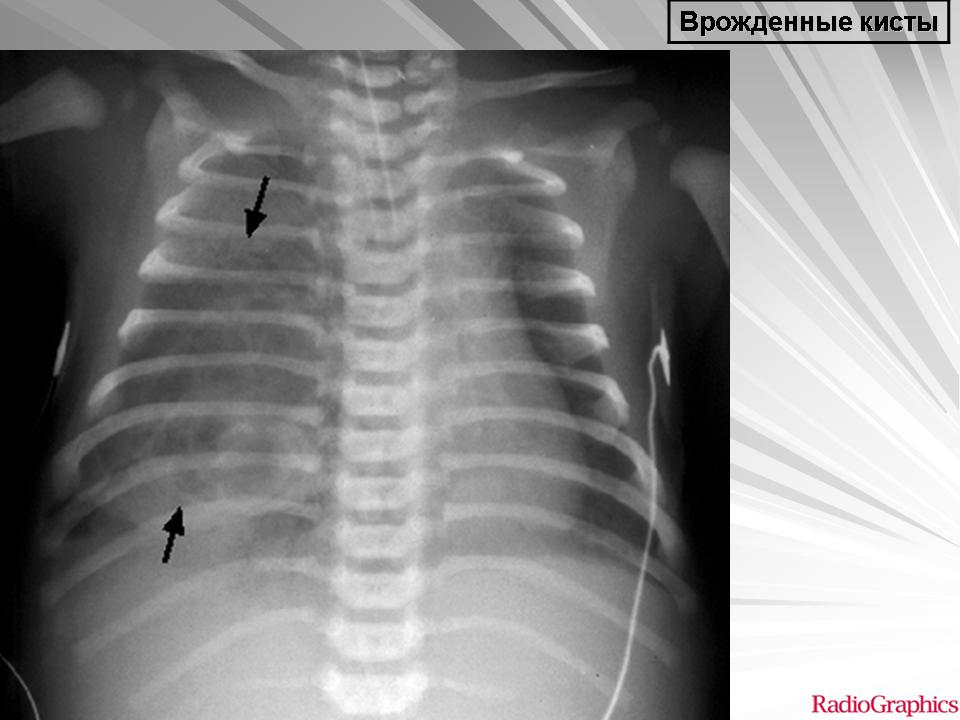

Легочные кисты.

Приложения:

1.ki_.slayd107.jpg2.ki_.slayd108.jpg3.ki_.slayd109.jpg